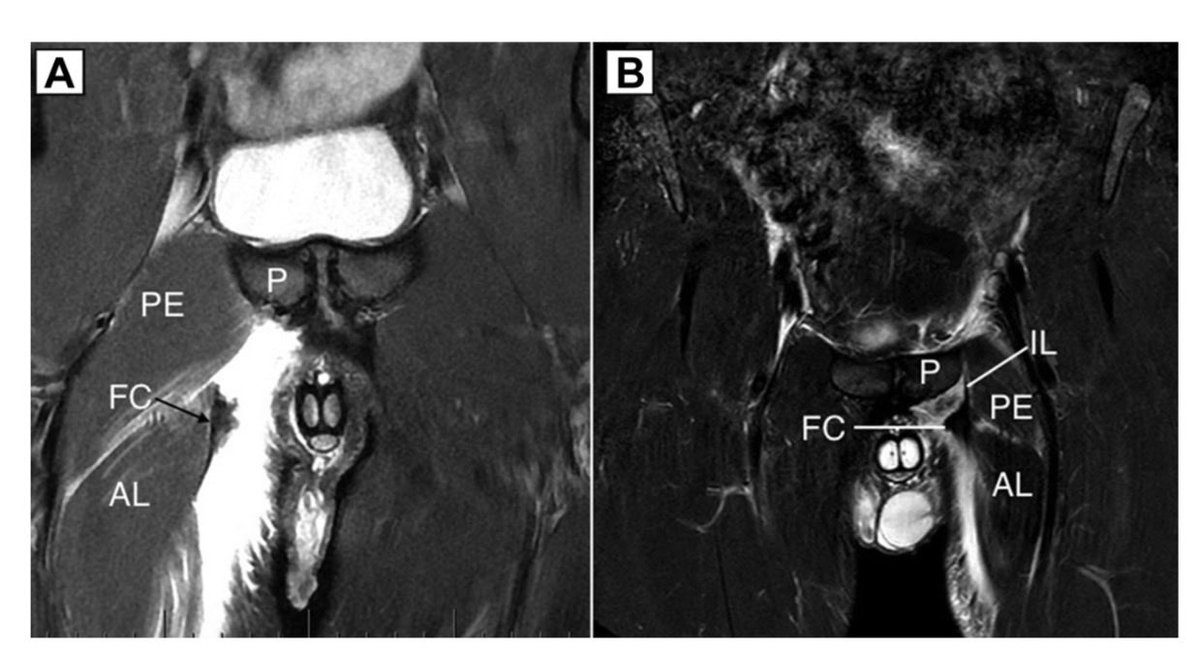

Proud to have contributed to this new AJSM paper on MRI assessment of PLAC (pyramidalis–adductor complex) injuries.